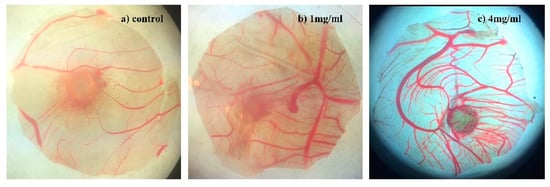

2.2.3. Angiogenesis Activity

3.2.5. Angiogenesis Assay